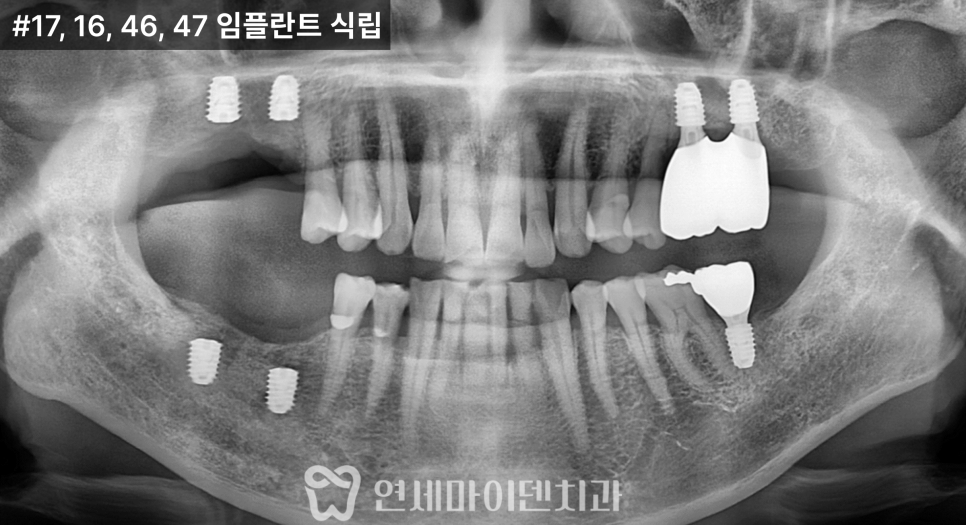

1차 수술: 발치, 염증 정리, 식립과 이식 동시 진행

첫 단계에서는

아래 1개, 위 2개

3개의 임플란트를 계획했습니다.

위쪽은 상악동이 내려와 있어

상악동 거상술과 뼈이식을 함께 시행한 뒤

그 공간에 임플란트를 식립했습니다.

아래쪽은 뼈 상태가 비교적 유지되어 있었지만

안정적인 고정을 위해

필요한 부위에 뼈이식을 병행했습니다.

2차 치료: 반대편 회복

시간이 지나면서

반대편도 불편감이 증가해

추가 치료를 진행하게 되었습니다.

위쪽 2개, 아래쪽 2개

4개의 임플란트를 계획했습니다.